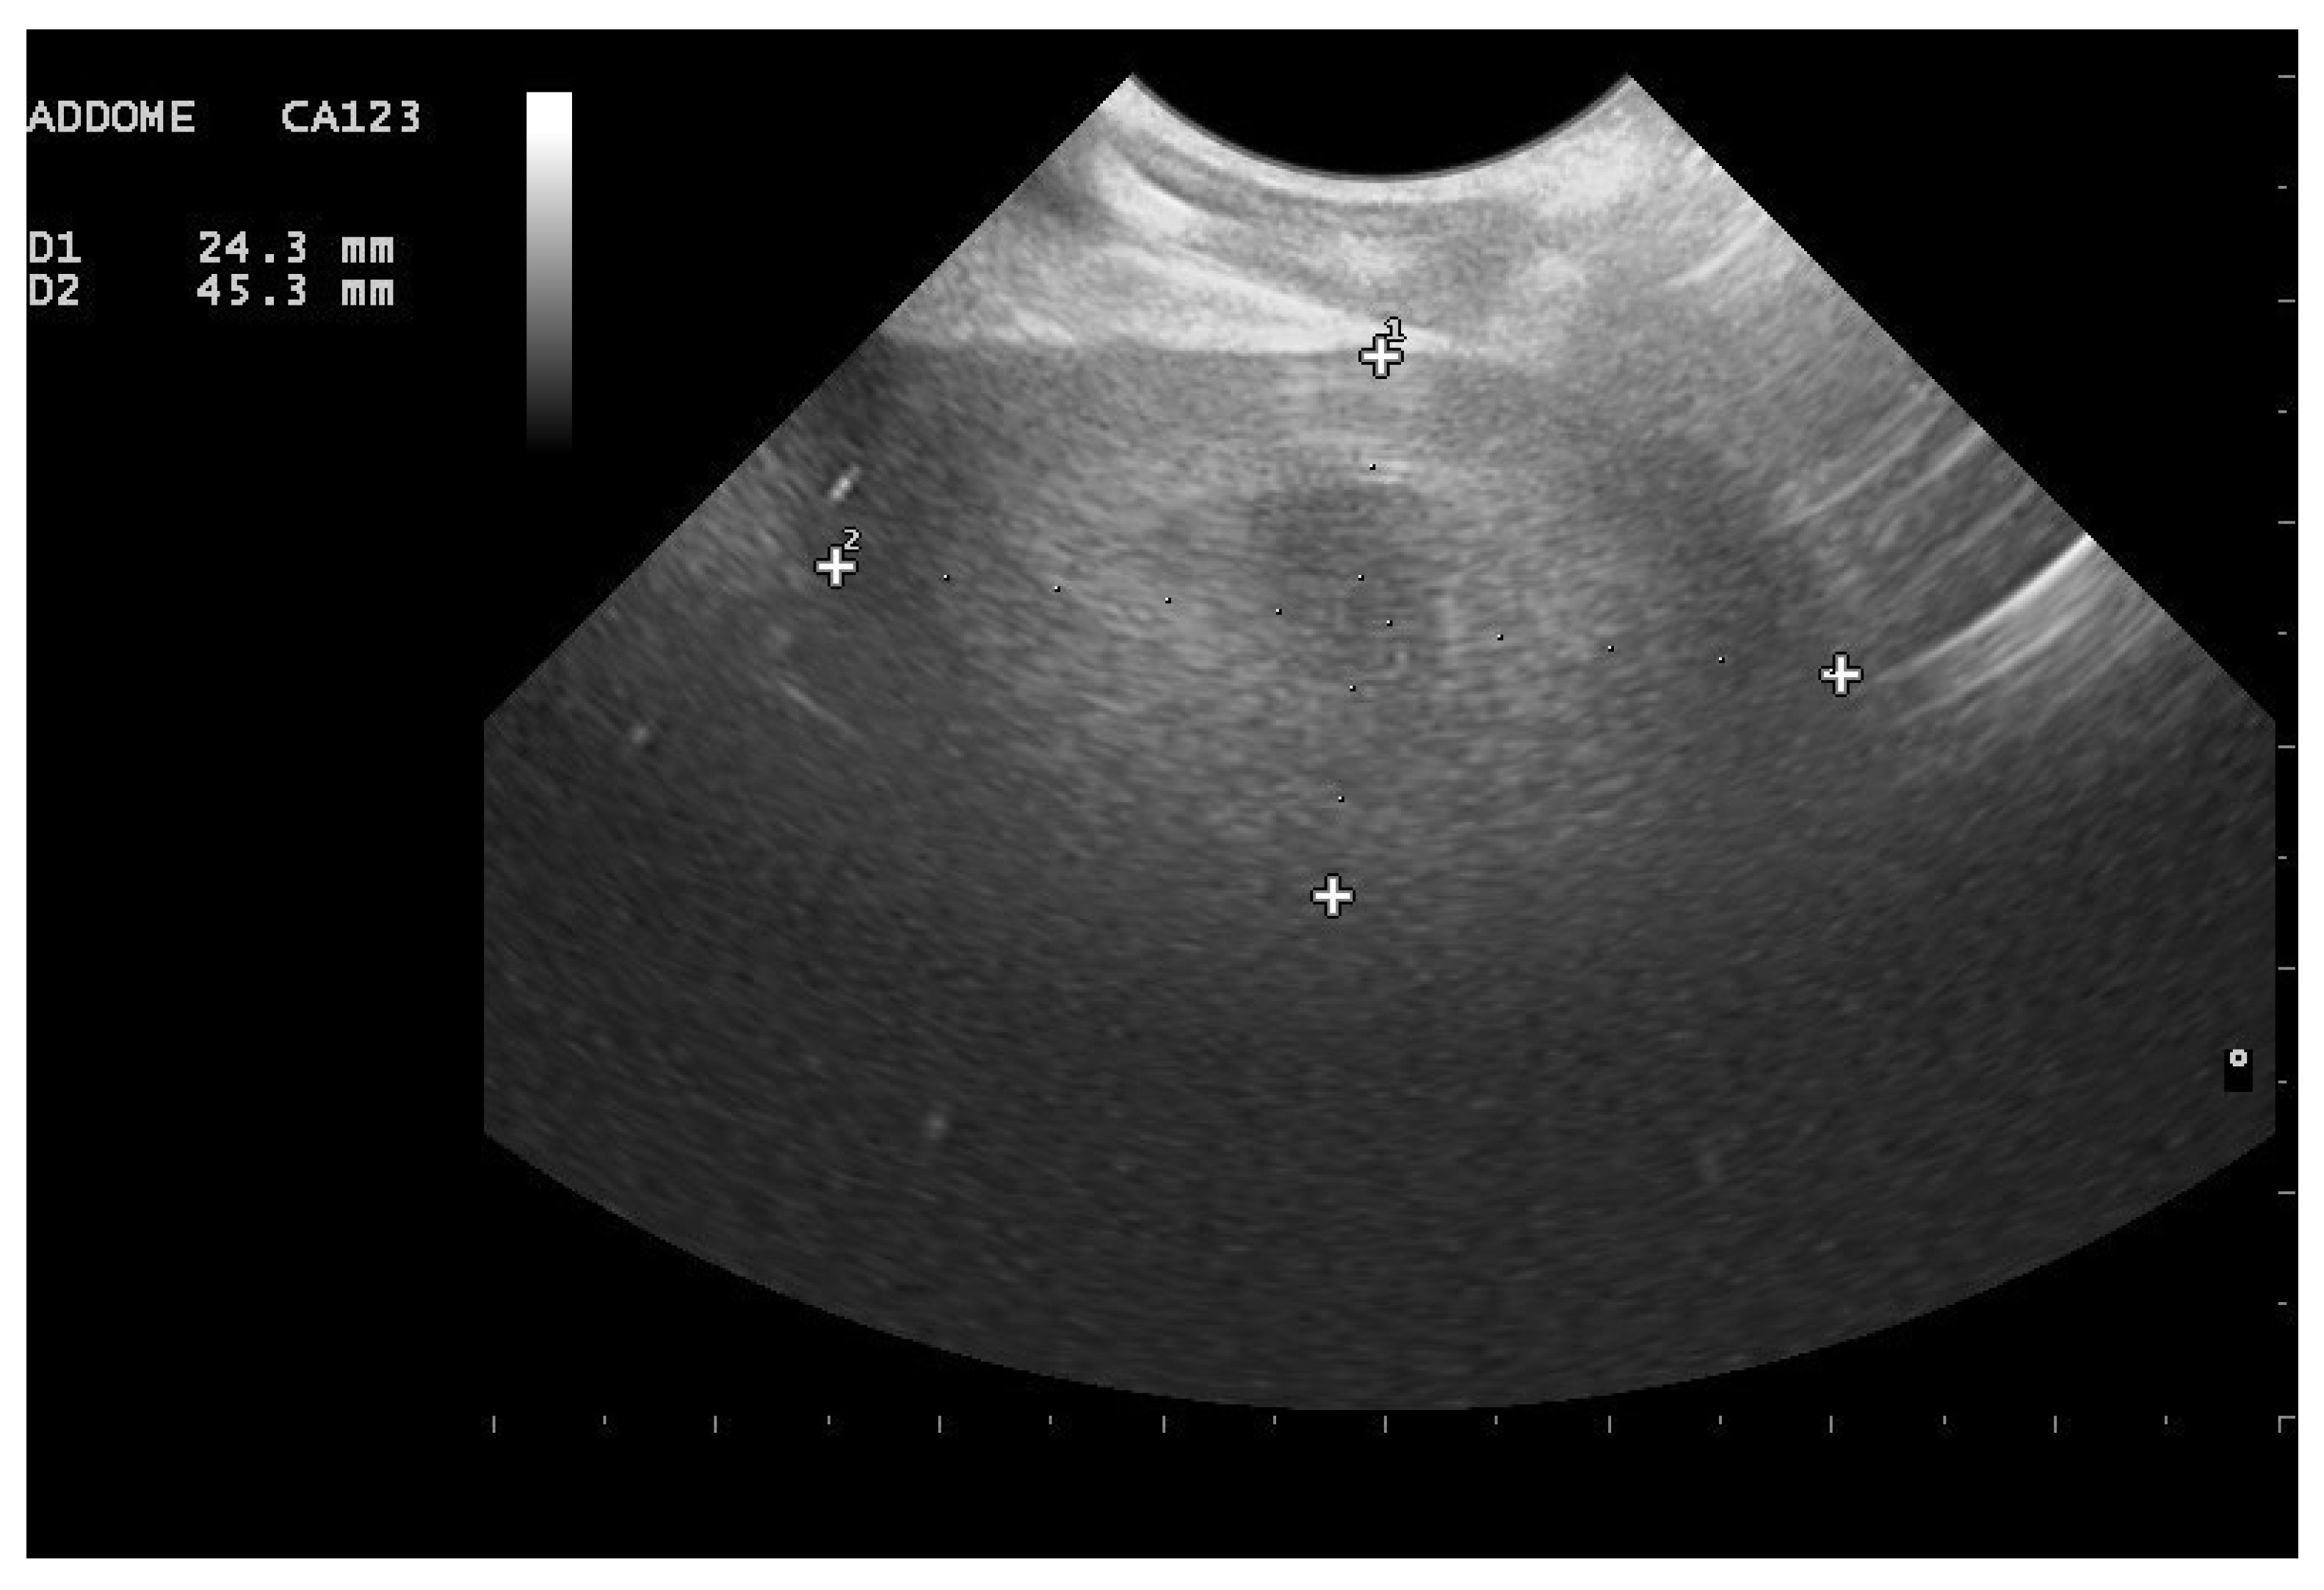

- Garcia, V.C.; Almeida-Santos, S.M. Reproductive cycles of neotropical boid snakes evaluated by ultrasound. Zoo Biol. 2021, 1–10. [Google Scholar] [CrossRef]

- Isaza, R.; Ackerman, N.; Jacobson, E.R. Ultrasound imaging of the coelomic structures in the Boa constrictor (Boa constrictor). Vet. Radiol. Ultrasound 1993, 34, 445–450. [Google Scholar] [CrossRef]